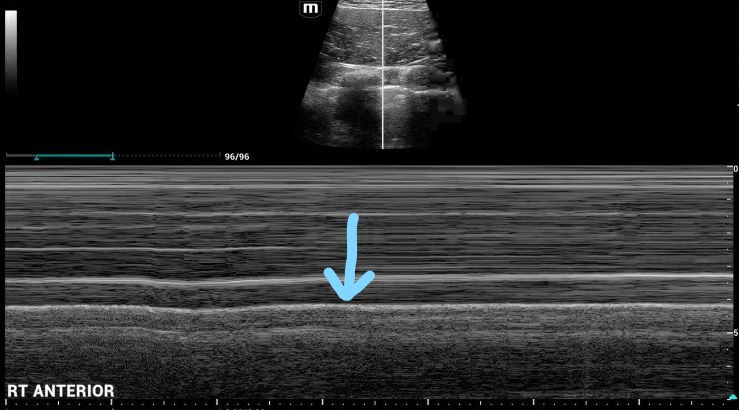

M-Mode Ultrasound Right (unaffected) lung: Interp: The blue arrow denotes the pleural line. Note the "waves on a beach" appearance below this line, indicative of lung sliding